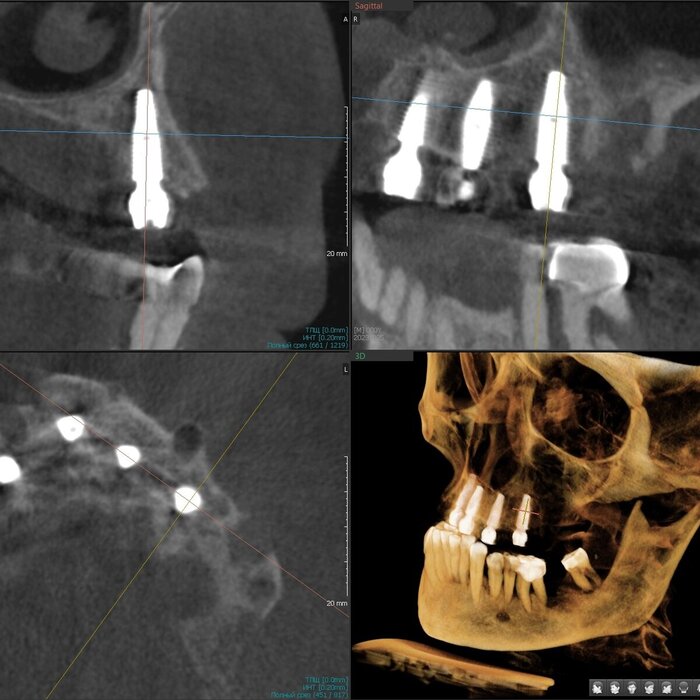

Как же всё-таки у нас происходит это мероприятие? Так как мы вмешиваемся в другую область нашего тела, то стоматолог должен быть хоть немного лором. Разумеется, всё начинается с обследования, которое включает в себя трехмерный снимок, который, в идеале должен захватывать не только зубы и область наращивания, но и носовые ходы с устьями гайморовых пазух и прочими загогулинами, то есть, так называемый остиомеатальный комплекс.

Поэтому кастрированный снимок, где видна только область установки будущего имплантата не прокатит. Тем более в центрах КТ такой снимок стоит дороже классической КТ рублей на 200. И стоит ли экономить?

Анализируя снимок, мы должны принять решение о том можно ли делать синус-лифтинг или отправить его на консультацию к лору. Если всё хорошо, то планируем операцию.

Если посмотреть рекомендации различных ассоциаций и изданий, то там сказано, то если толщина остаточной кости составляет до 5-8 мм, то надо делать открытый синус-лифтинг, если более, то закрытый.

Я делаю транскрестальный синус-лифтинг в 95% случаев последние пару лет, даже если толщина кости меньше 1 миллиметра, но, за счет опыта понимания свойств слизистой гайморовой пазухи наощупь и использования определенных материалов непосредственно в процессе, могу поднять её, зачастую, более чем на 10 мм через дырку диаметром всего 4-5 мм без разреза десны на половину челюсти. Причем, как правило, без использования молотка. Как-то так.

Соответственно разрез меньше, рожа потом практически не распухает, процедура проходит комфортнее, несмотря на её техническую сложность. К тому же мы забываем про риск кровотечения из задней верхней альвеолярной артерии, которая проходит как раз в толще стенки пазухи и часто повреждается при классическом открытом синус-лифтинге. В плане затрат на материал тоже выгоднее, можно сэкономить как собственные деньги, так и деньги пациента. Однако, в голове надо держать то, что данный вид синус-лифтинга требует высоких мануальных навыков врача, ювелирной точности, а также смелости, так как тут шаг влево, шаг вправо-расстрел. Также в любой момент в случае чего нужно быть готовым перевести свой синус-лифтинг в открытый.